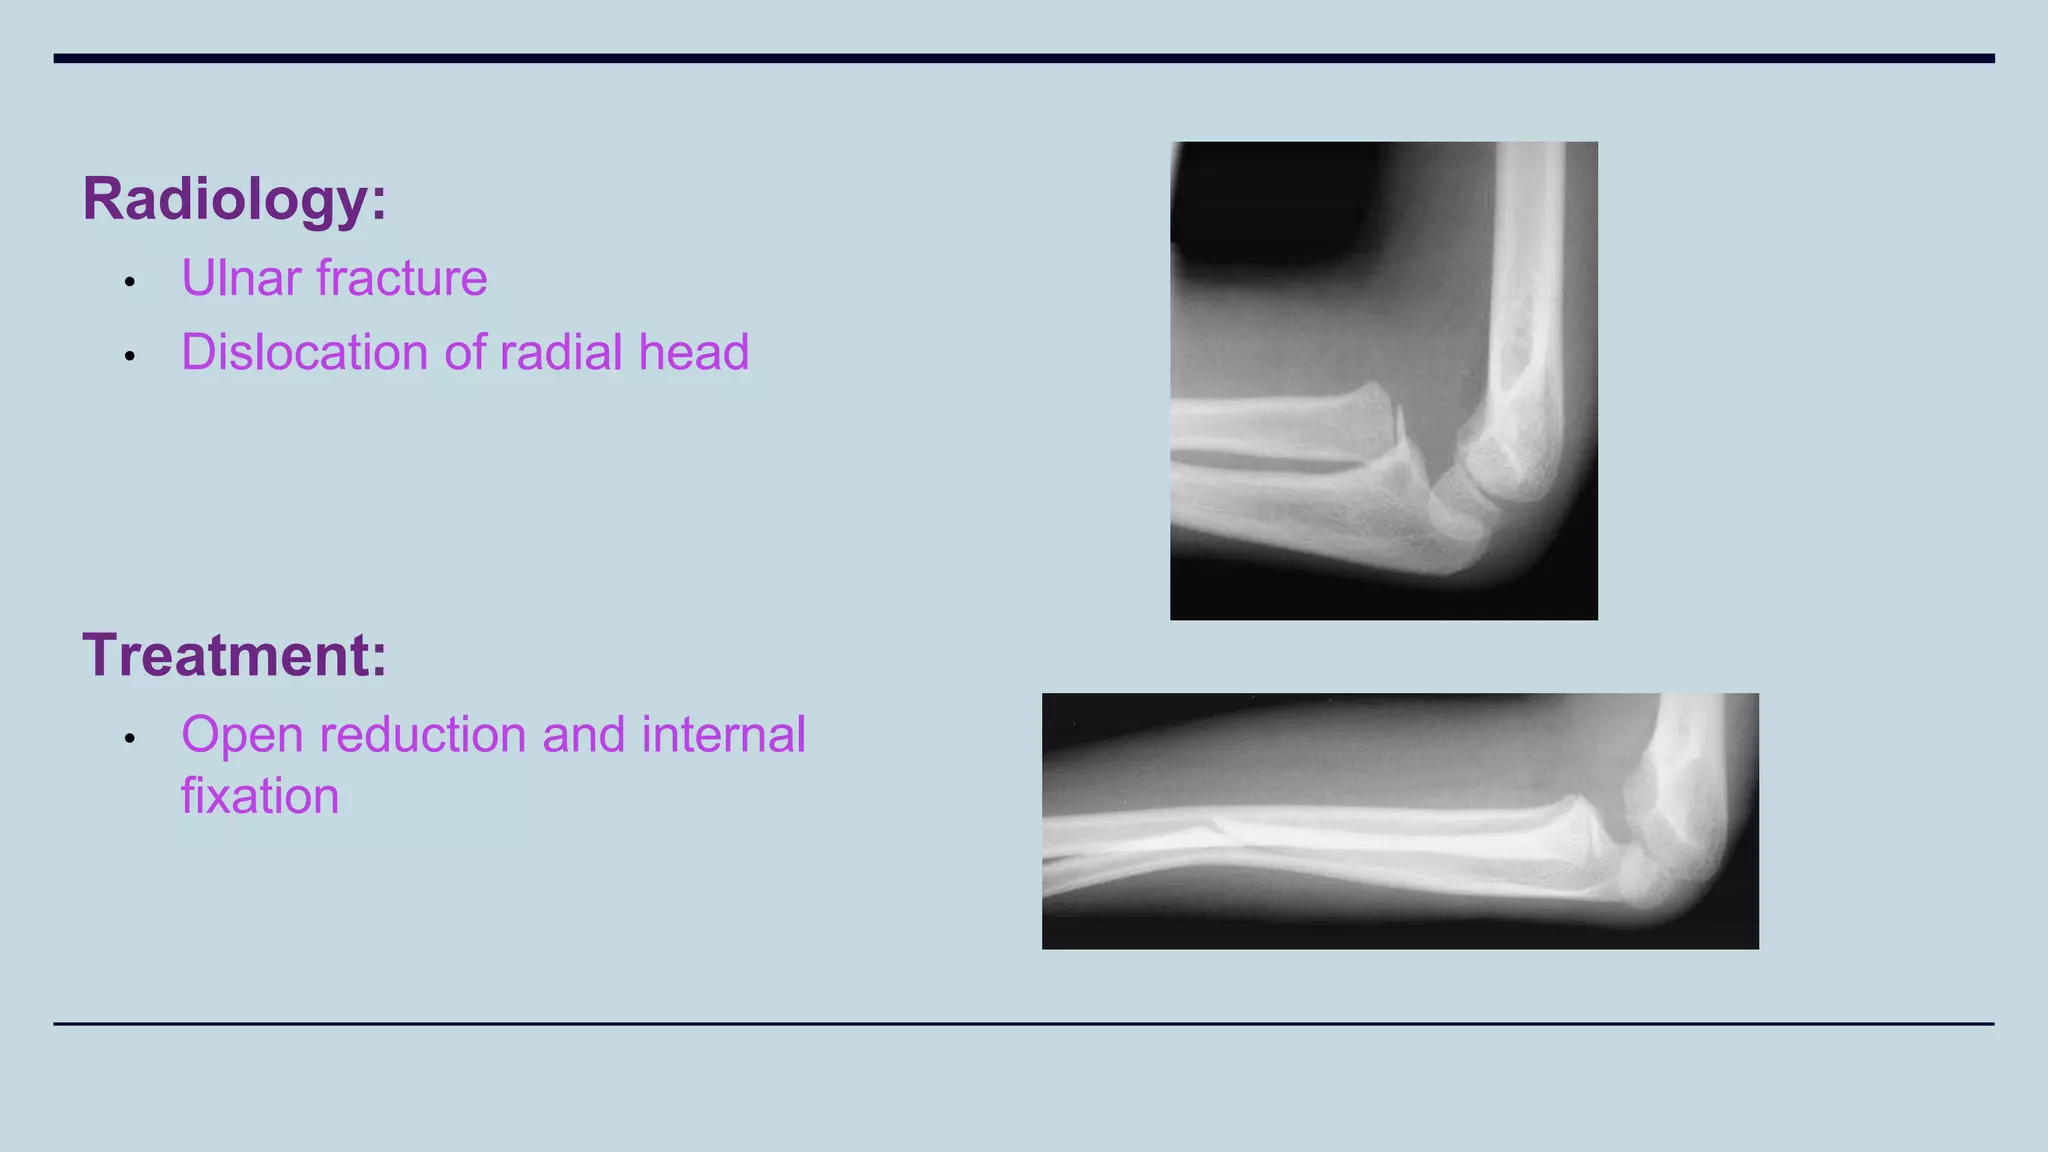

Monteggia’s Fracture

Radiology:

• Ulnar fracture

• Dislocation of radial head

Treatment:

• Open reduction and internal

fixation